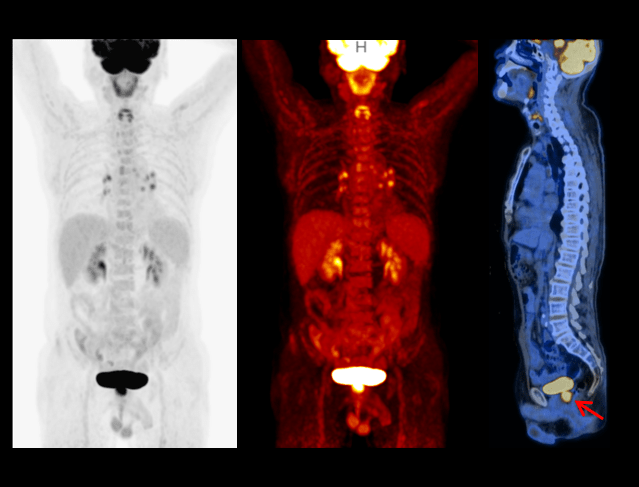

Galerie clinică

Limfom

Tehnologia PET/CT digitală joacă un rol crucial în diagnosticarea și monitorizarea limfomului, oferind imagini de înaltă rezoluție pentru detectarea leziunilor și evaluarea eficienței tratamentului.